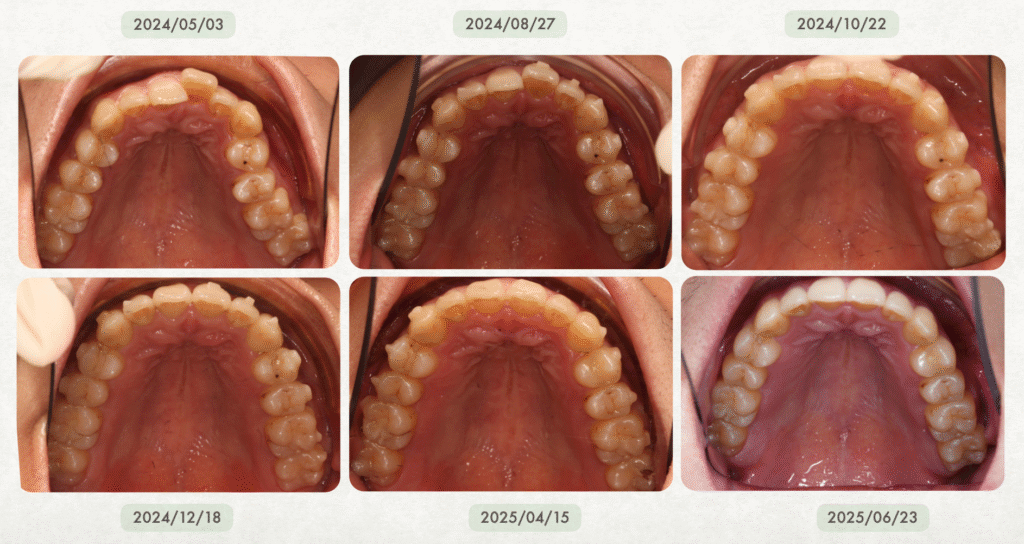

真實案例:隱適美有時甚至比傳統矯正還快!

在輕度到中度牙齒凌亂的案例中,隱適美不但不慢,反而更有效率、更快完成。

- 若配戴配合度良好,療程甚至可能在一年內順利完成

很多人驚訝地發現:「原來隱適美也可以這麼快!」

在 沐森美學牙醫 的實際經驗中,隱適美治療並不會特別久,甚至在某些案例中,反而可以比傳統矯正更有效率、完成得更快✨!

尤其在輕度到中等牙齒凌亂的情況下,隱適美有非常大的機會比傳統矯正更快速完成喔~而且費用也跟傳統矯正差不多!